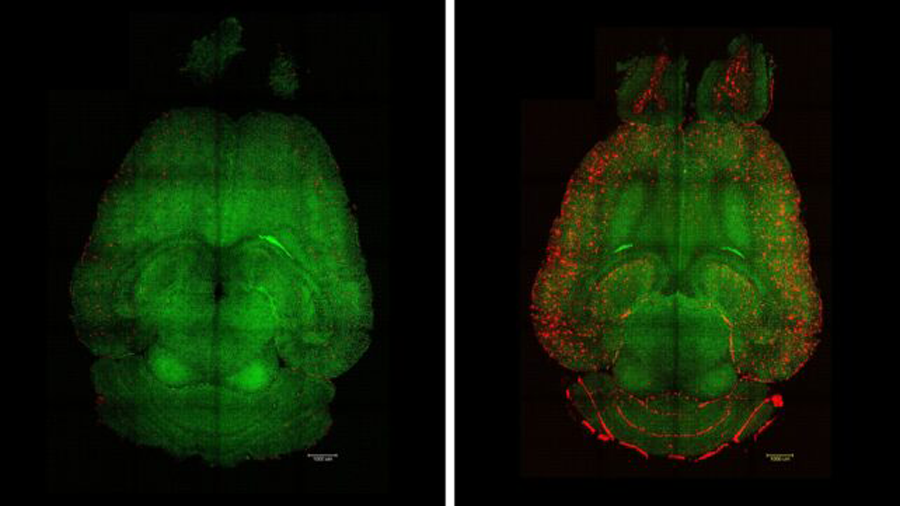

دانشمندان موفق شدهاند مسیر طبیعی ورود به مغز موشها را ترمیم کنند؛ اقدامی که امکان پاکسازی تودهها و گرههای مرتبط با بیماری آلزایمر را فراهم کرده است. تنها پس از سه بار تزریق دارو، در موشهایی که دارای ژنهای مشابه بیماران آلزایمری بودند، نشانههای اصلی این بیماری بهطور چشمگیری معکوس شد.

در فاصله چند ساعت پس از نخستین تزریق، مغز حیوانات آزمایشگاهی کاهش نزدیک به ۴۵ درصدی در تجمع پلاکهای آمیلوئید بتا که از شاخصهای اصلی بیماری آلزایمر محسوب میشود، نشان داد. موشها پیش از درمان علائم افت شناختی داشتند، اما پس از دریافت هر سه دوز دارو، عملکرد آنها در آزمونهای یادگیری فضایی و حافظه با موشهای سالم برابر شد. آثار این بهبود دستکم تا شش ماه پایدار ماند.

به گفته تیم بینالمللی پژوهشگران، در بیماری آلزایمر، مشکل تنها محدود به دسترسی نیست؛ بلکه خود سامانهی انتقال در مغز نیز بهطور بیماریزا دچار اختلال عملکرد شده است. دانشمندان در این مطالعه از نانوذرات نه بهعنوان حاملهای غیرفعال دارو، بلکه بهعنوان عوامل فعال تغییر استفاده کردند و از این طریق توانستند جریان عبور مواد از سد خونی-مغزی را اصلاح کرده و فرآیند پاکسازی پلاکهای آمیلوئیدی را در مغز موشها بازگردانند.

جوزپه باتالیا، مهندس زیستی از مؤسسه مهندسی زیستی کاتالونیا (IBEC)، توضیح میدهد: «تأثیر بلندمدت این روش از طریق بازسازی رگهای خونی مغز حاصل میشود. تصور ما این است که این روند مانند یک زنجیره عمل میکند: زمانی که مواد سمی مانند آمیلوئید بتا تجمع مییابند، بیماری پیشرفت میکند. اما هنگامی که سیستم عروقی دوباره توان عملکرد طبیعی خود را به دست آورد، شروع به پاکسازی آمیلوئید بتا و دیگر مولکولهای مضر میکند و در نتیجه کل سامانه به تعادل بازمیگردد.»